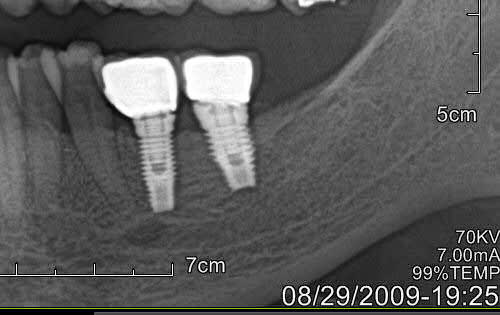

J'ai eu le cas sur une patiente avec implants sans probleme depuis 2006, debut de craterisation en 2014.

J'ai utilise le tourne a gauche d'anthogyr, et malgre le detourage a la fraise sur la profondeur la plus grande possible, j'ai bien cru que soit l'instrument soit la mandibule allaient rompre.

En fait ca ressort quand l'os autour de l'implant se rompt dans son epaisseur. L'os est reste collé sur l'implant retire.

Image1 juplas - Eugenol

Image2 nvyecp - Eugenol